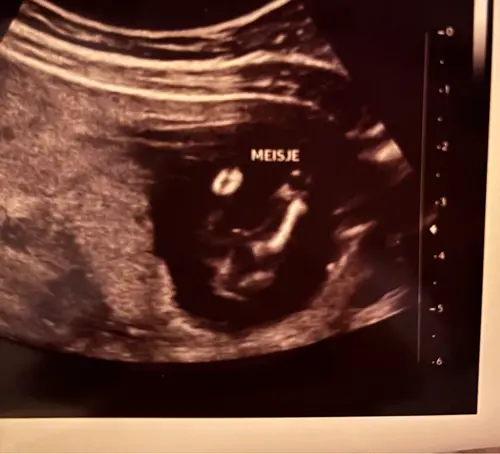

Ik had met de 13 weken echo hier een foto geplaatst waarop de Nub goed te zien was, bijna iedereen dacht dat het een meisje was waarvan een paar zelfs helemaal overtuigd. Twee personen zeiden een jongetje en wat bleek vandaag inderdaad een jongen 🤣😂😂.

Zo zie je maar de nub beoordelen zegt niet alles. We zijn hartstikke blij met een jongen overigens hoor! 😁😁

Is dit duidelijke een meisje? Door de nub dachten we namelijk eerst een jongen